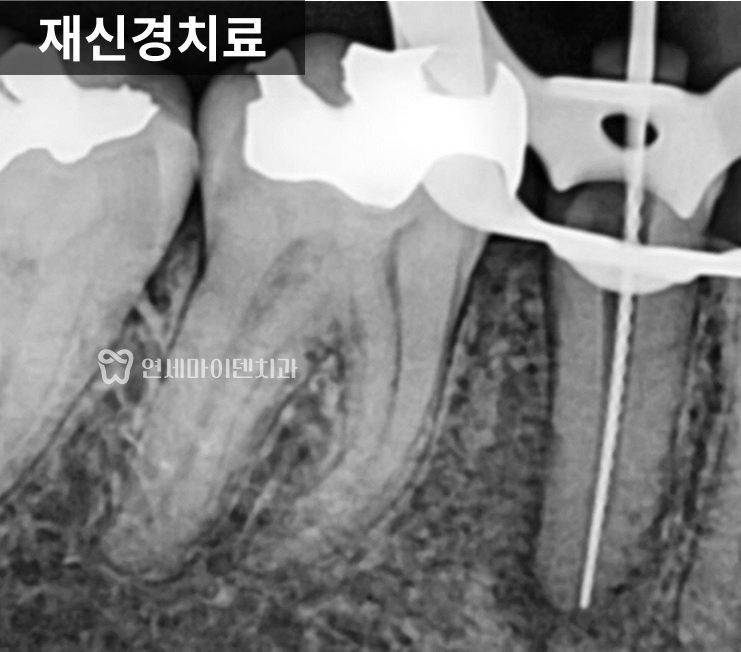

근본적인 치료, 재신경치료

이 치아를 살리기 위해

선택한 치료는 재신경치료였습니다.

미세현미경을 이용해

기존 신경치료에서

도달하지 못했던 뿌리 끝까지 접근

세균을 철저히 제거하고

내부를 깨끗하게 소독한 뒤

다시 밀폐했습니다.

치료 후 회복 과정

재신경치료 후

불과 2~3주 만에

잇몸 여드름은 자연스럽게 사라졌고,

몇 달이 지나면서

녹아 있던 뼈도

점차 다시 차오르는 모습

확인할 수 있었습니다.